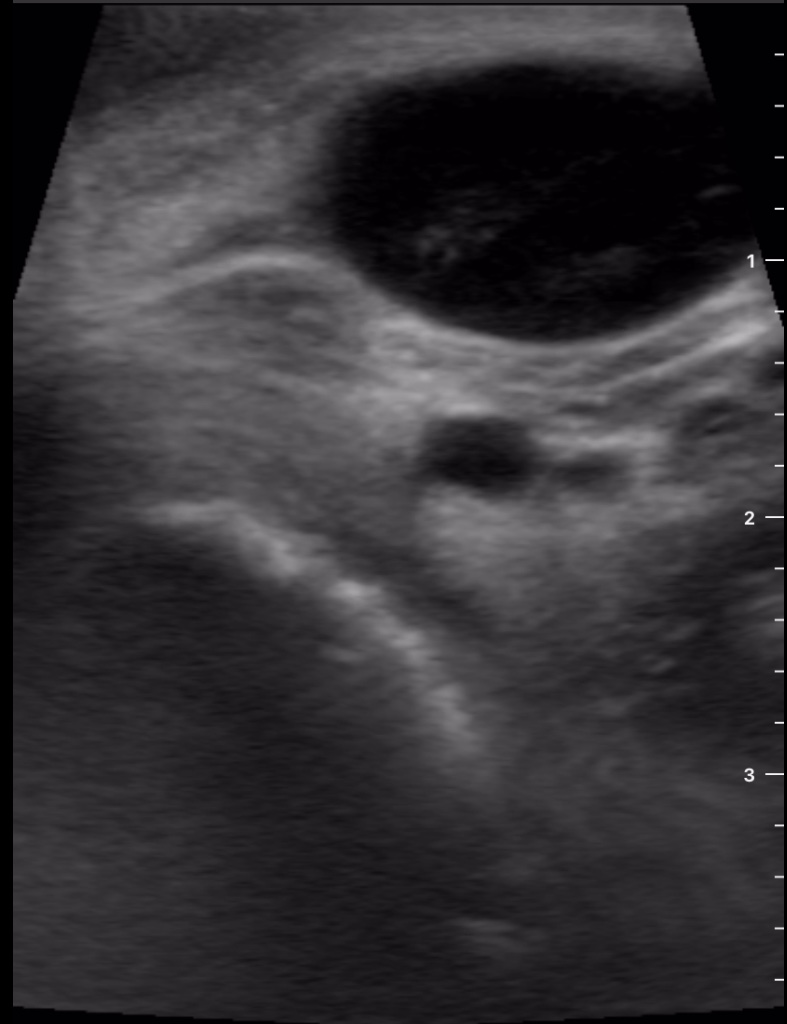

Se decide realizar ecografía clínica con ecógrafo de bolsillo para poder orientar caso, donde se aprecia tumoración de gran tamaño hipoecoica, heterogénea, con calcificaciones de pequeño tamaño en su interior, dependiente de lóbulo tiroideo derecho, sin poder definir límites inferiores, y sin poder localizar la vena cava inferior pero visualizando imagen de vena trombosada junto al istmo.